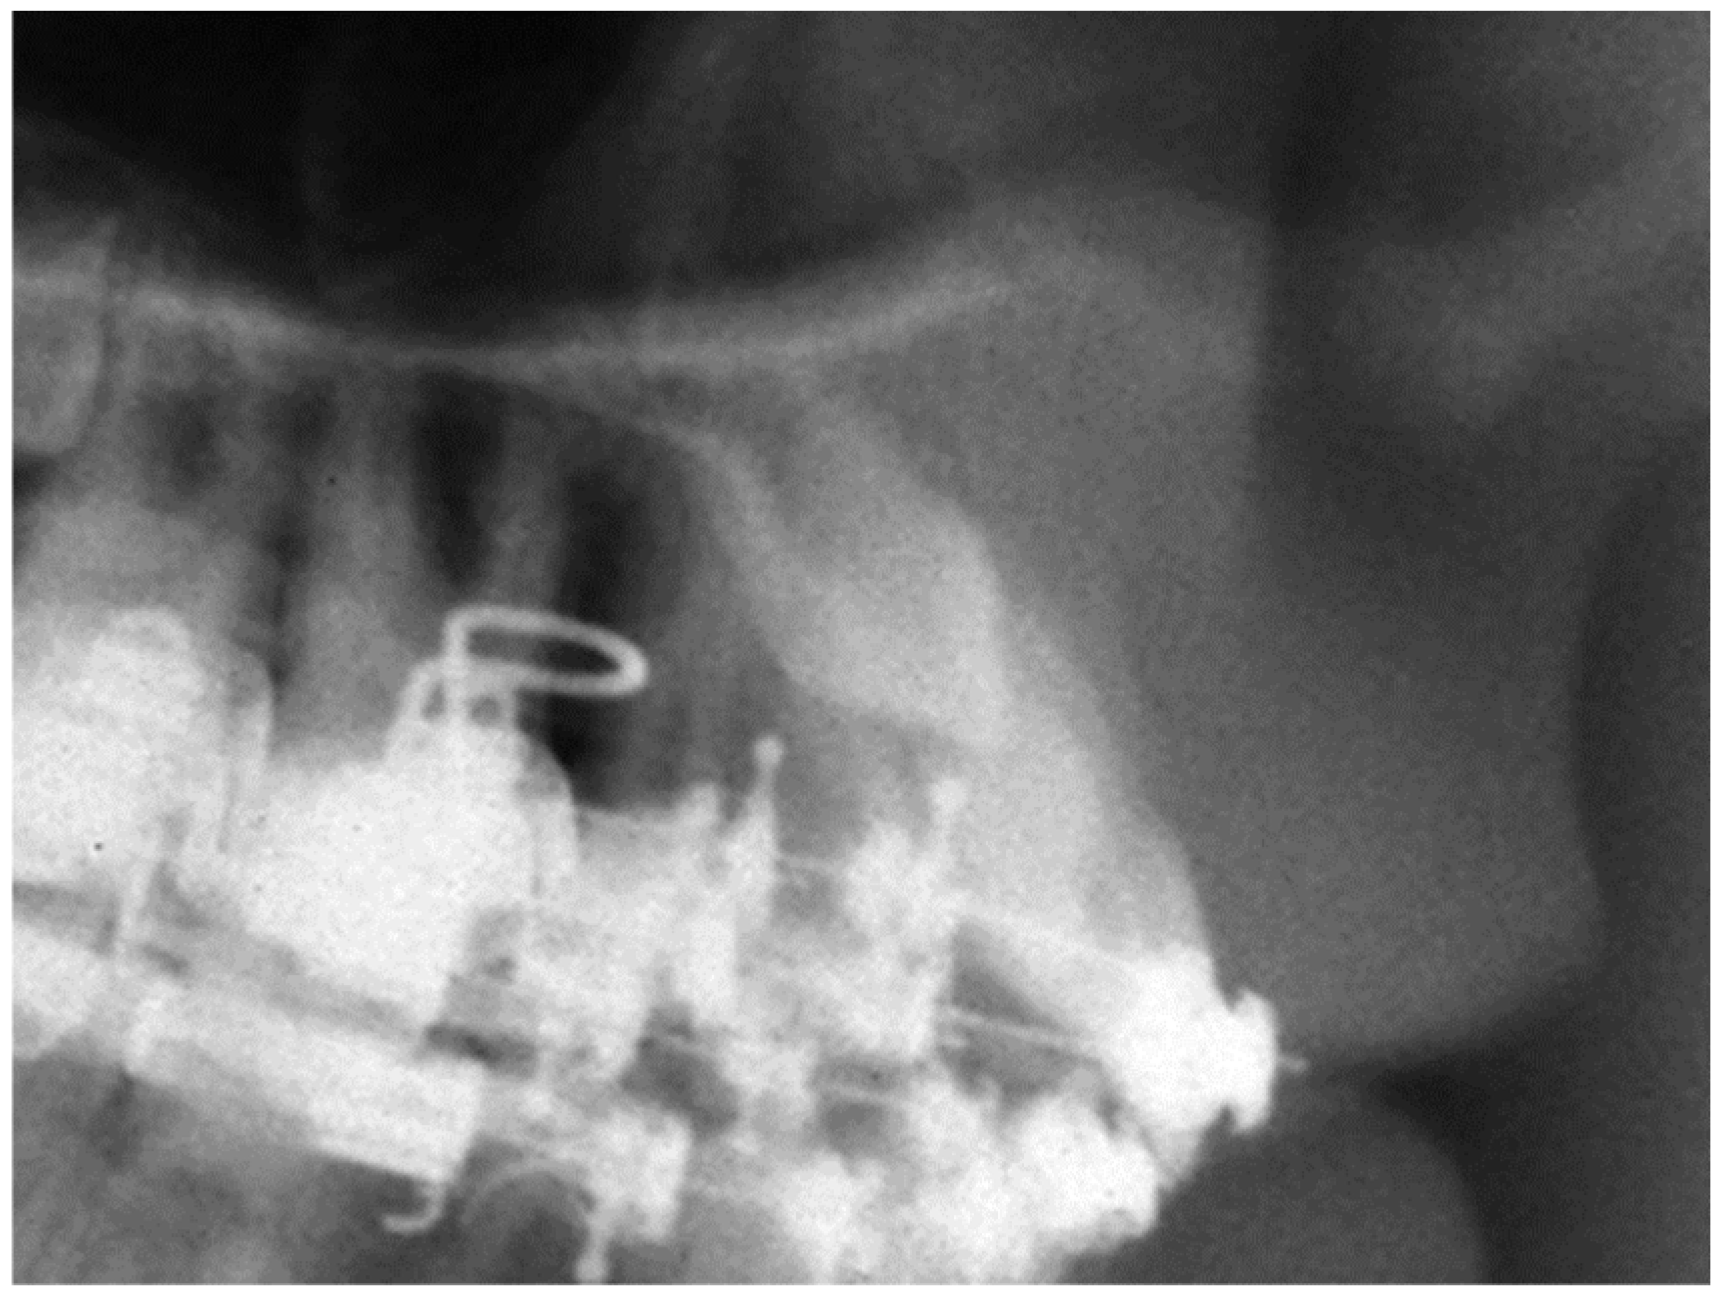

Two-Dimensional Radiographic Diagnosis of Maxillary Canine Impactions

2.2. Data Collection

2.3. Data Analysis